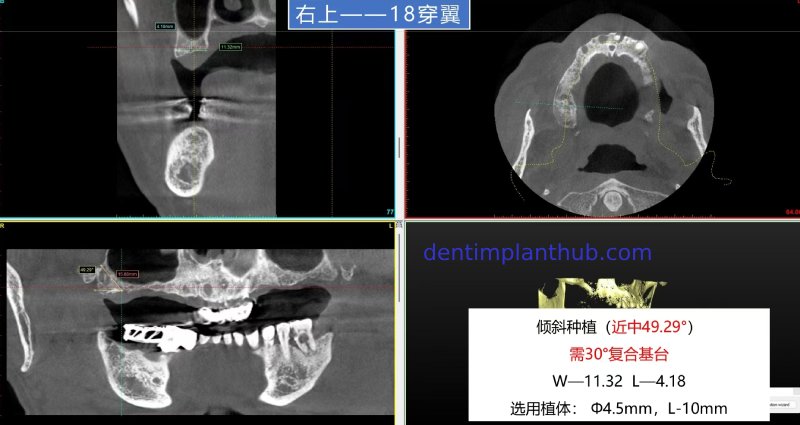

The specific conditions of each tooth position and the implant plan

For tooth 18, with a width of 11.32 and a height of 4.18, an implant with a diameter of 45 and a length of 10 is selected. It needs to be implanted at an inclination. The mesial angle is 49.29°, and a 30° composite abutment is required.